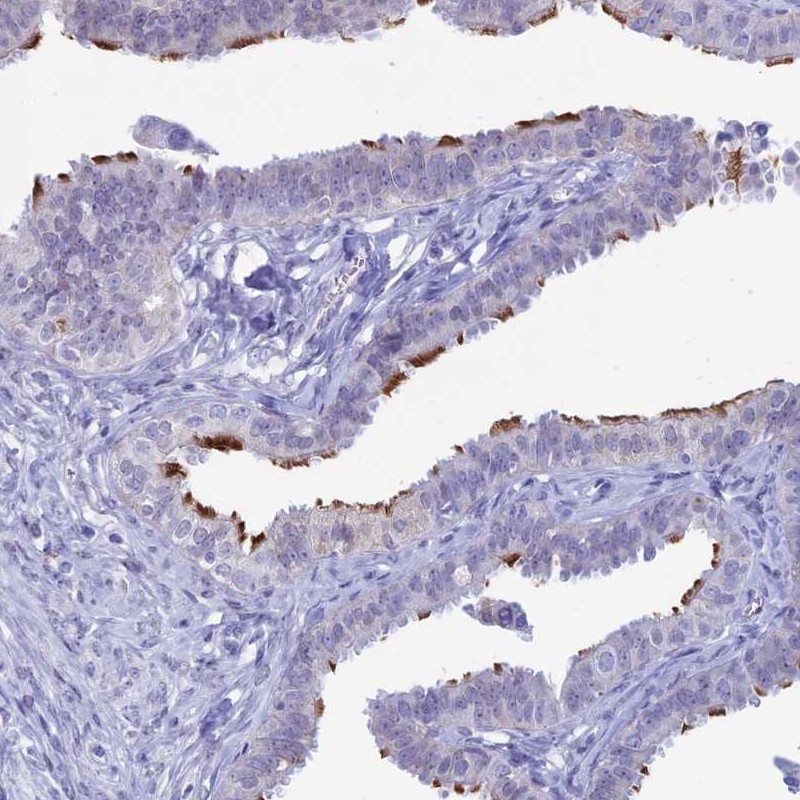

Immunohistochemical staining of human fallopian tube shows distinct positivity in cilia.